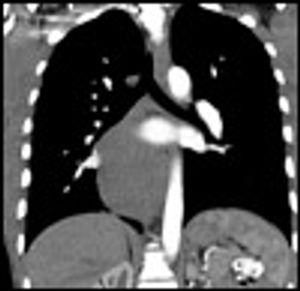

A 24-year-old man with an unremarkable medical history presented to the emergency department with abdominal pain and hematemesis of 3 days' duration. His symptoms were postprandial, and each episode yielded up to half a cup of blood without clots. He denied using NSAIDs or alcohol. He had had an episode of hematemesis 2 years earlier that resolved spontaneously, for which he had not sought treatment. His vital signs were normal, and his physical examination was notable only for moderate epigastric tenderness without rebound or guarding.